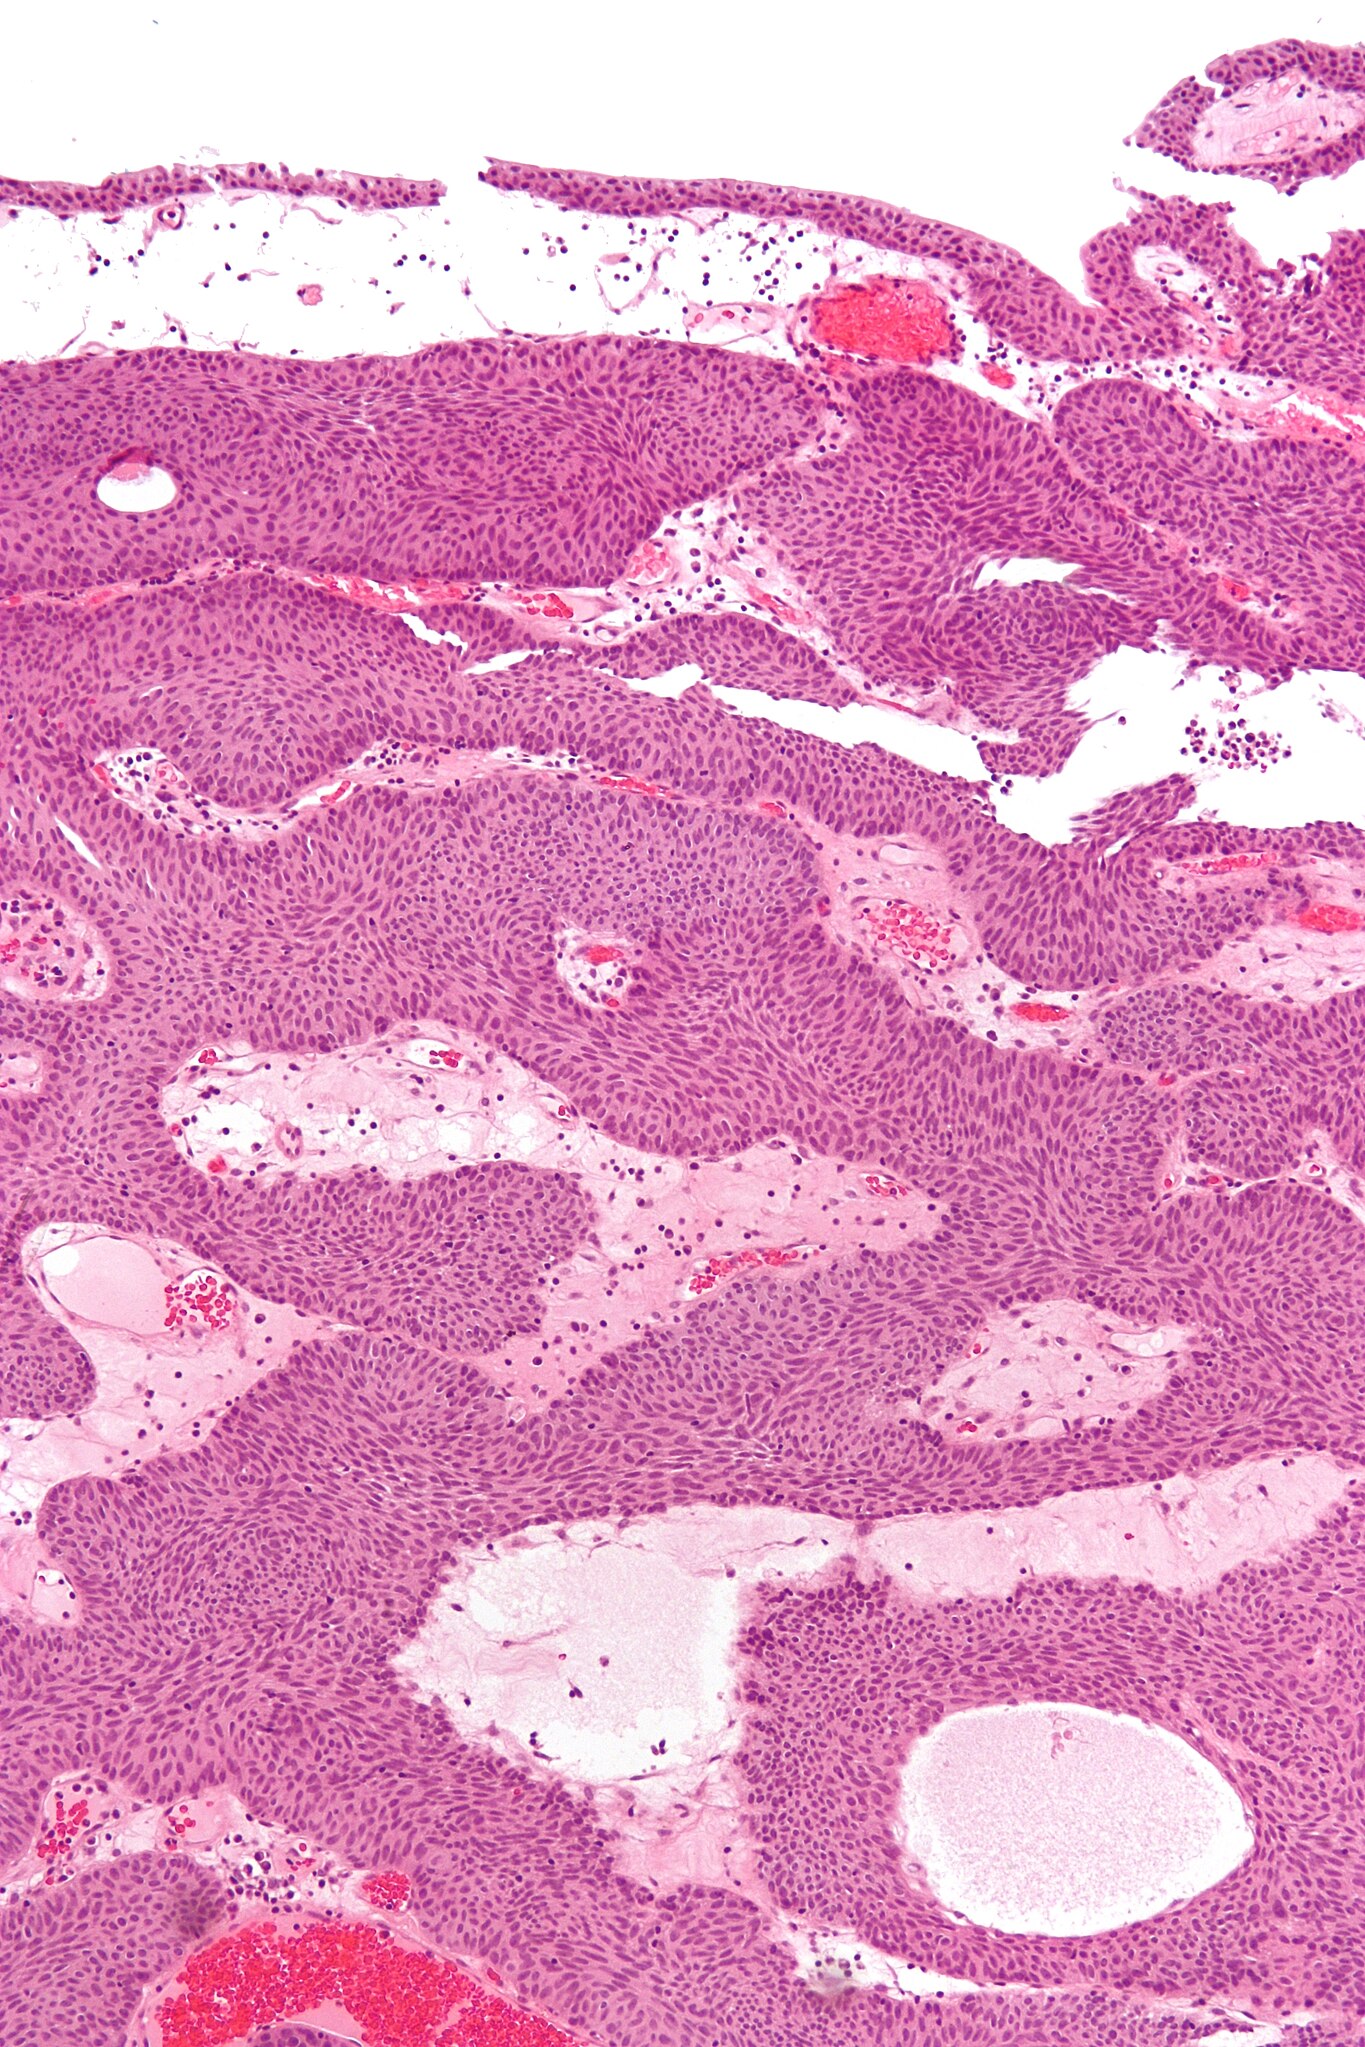

English: High magnification micrograph of an inverted papilloma. H&E stain.

This entity may be confused with an invasive urothelial carcinoma; features that differentiate these entities and suggest malignancy are the presence of:

1. Mitoses.

2. Atypical mitosis.

3. Nuclear atypia (variable nuclear size, shape and staining).

4. Stromal invasion/desmoplastic stroma.